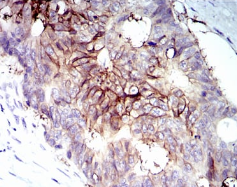

IGF1R-Beta Mouse Monoclonal antibody[3G5C1]

IGF1R(insulin-like growth factor 1 receptor), a transmembrane receptor tyrosine kinase, is widely expressed in many cell types within fetal and postnatal tissues, and in many cell lines. Upon binding to its ligands, IGF-I and IGF-II, receptor autophosphorylation occurs. The triple tyrosine cluster within the kinase domain (Tyr1131, Tyr1135 and Tyr1136) is the earliest major site of autophosphorylation. Phosphorylation of these three tyrosine residues is necessary for kinase activation.Insulin receptors (IRs) share significant similarity with IGF1 receptors in both structure and function,including an equivalent triple tyrosine cluster within the activation loop of the kinase domain (Tyr1146, Tyr1150 and Tyr1151).Tyrosine autophosphorylation of insulin receptor is one of the earliest cellular responses to insulin stimulation. Autophosphorylation begins with phosphorylation of Tyr1146 and either Tyr1150 or Tyr1151. Full kinase activation requires the triple tyrosine phosphorylation.

Immunogen :   Purified recombinant fragment of IGF1R-Beta (AA: 1101-1367) expressed in E. Coli.

IHC    1/200 - 1/1000